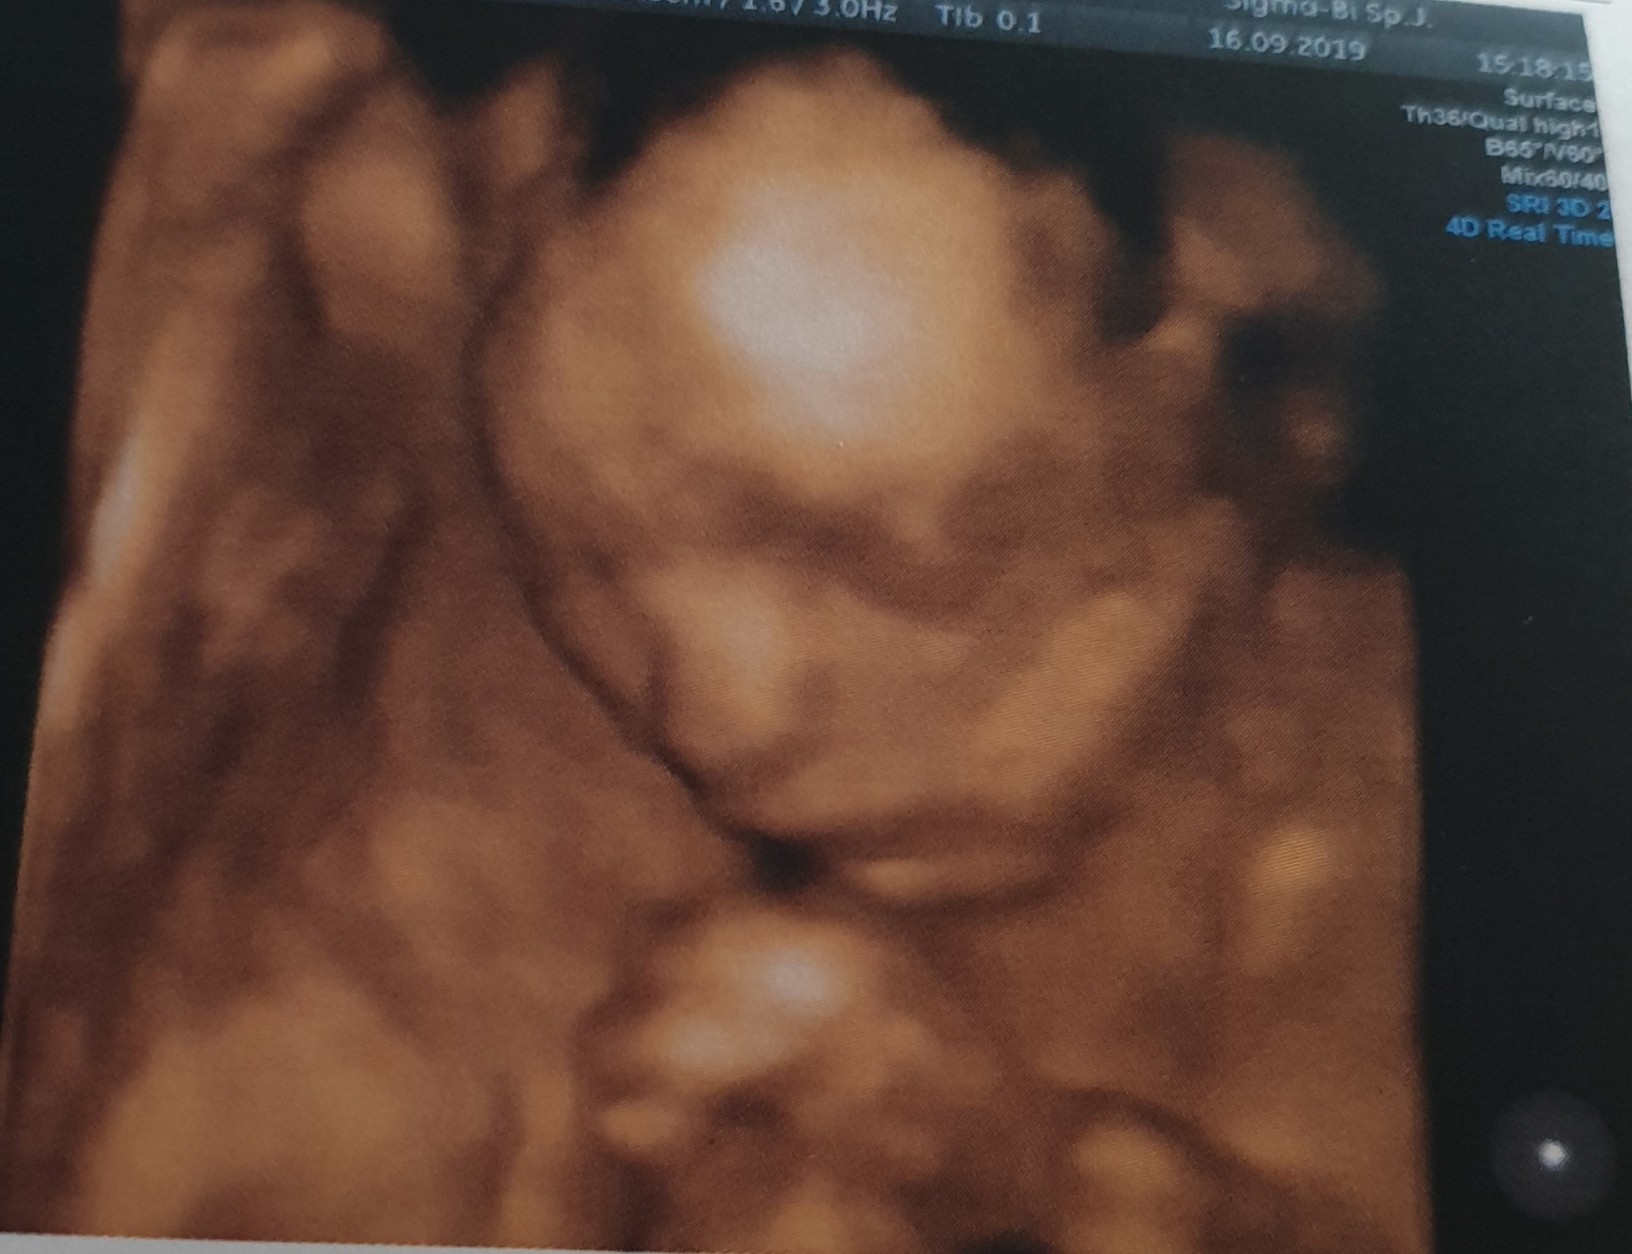

Hej dziewczyny my po prenatalnych.Koniec złudzeń 100%chłopak.Wszystkie parametry ok.Waga 487g (OM 21+1 a z usg 21+6).Cieszę się bardzo,że zdrowy.Jeszcze pozostaje mi uporać się z moją głową,w której siedzi myśl o niespełnionym marzenie o córeczce.